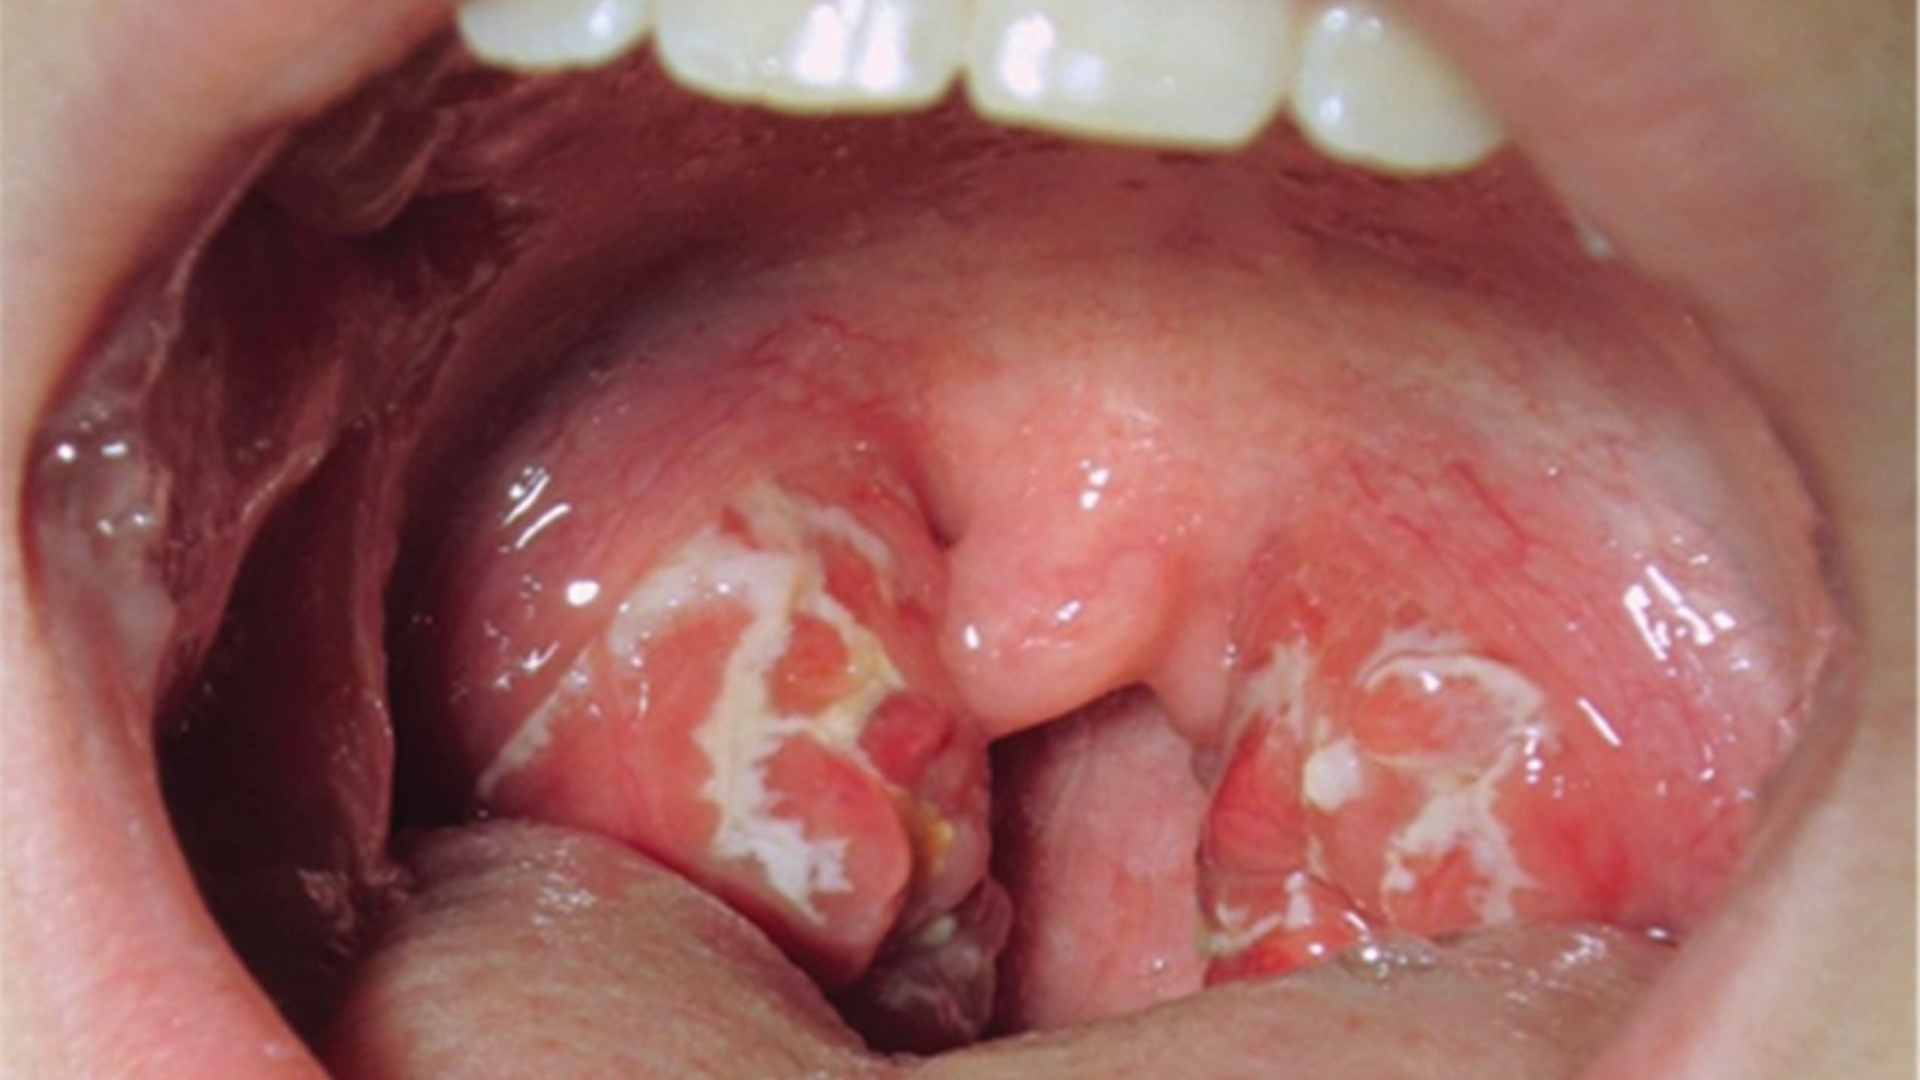

口咽癌(喉癌)是發生在口咽組織的侵襲性癌症,口咽組織包括扁桃腺、軟顎、舌根和咽壁。這種癌症主要是內層的鱗狀細胞發生惡性變化。每年全球有數以千計的人被診斷出罹患口咽癌(喉癌),對他們的生活品質和情緒健康造成深遠的影響。瞭解此種疾病可增強患者和家屬的能力,並透過明智的治療選擇和早期檢測,為他們帶來希望。

口咽癌(喉癌)的症狀

認識口咽癌(喉癌)的早期症狀可確保及時診斷,增加成功治療的機會。根據疾病的階段和腫瘤在喉嚨或口咽部結構內的位置,症狀會有很大的差異。

口咽癌(喉癌)早期症狀

• 疼痛或無痛的持續性喉嚨痛持續兩週以上

• 感覺喉嚨或頸部有腫塊,且無法自然消退

• 吞嚥困難(吞嚥困難),尤其是固體食物

• 聲音明顯改變或持續性聲音沙啞

• 慢性咳嗽,有時伴有微量帶血的痰液

• 共用神經通路導致的耳痛(轉介性耳痛)

• 不明原因的體重下降和食慾不振

當發現上述一種或多種症狀時,應立即進行醫療評估,以排除口咽癌(喉癌)的可能性,或在早期階段尋求有效的治療。早期發現和即時介入對於確保患者的最佳療效和長期康復至關重要。